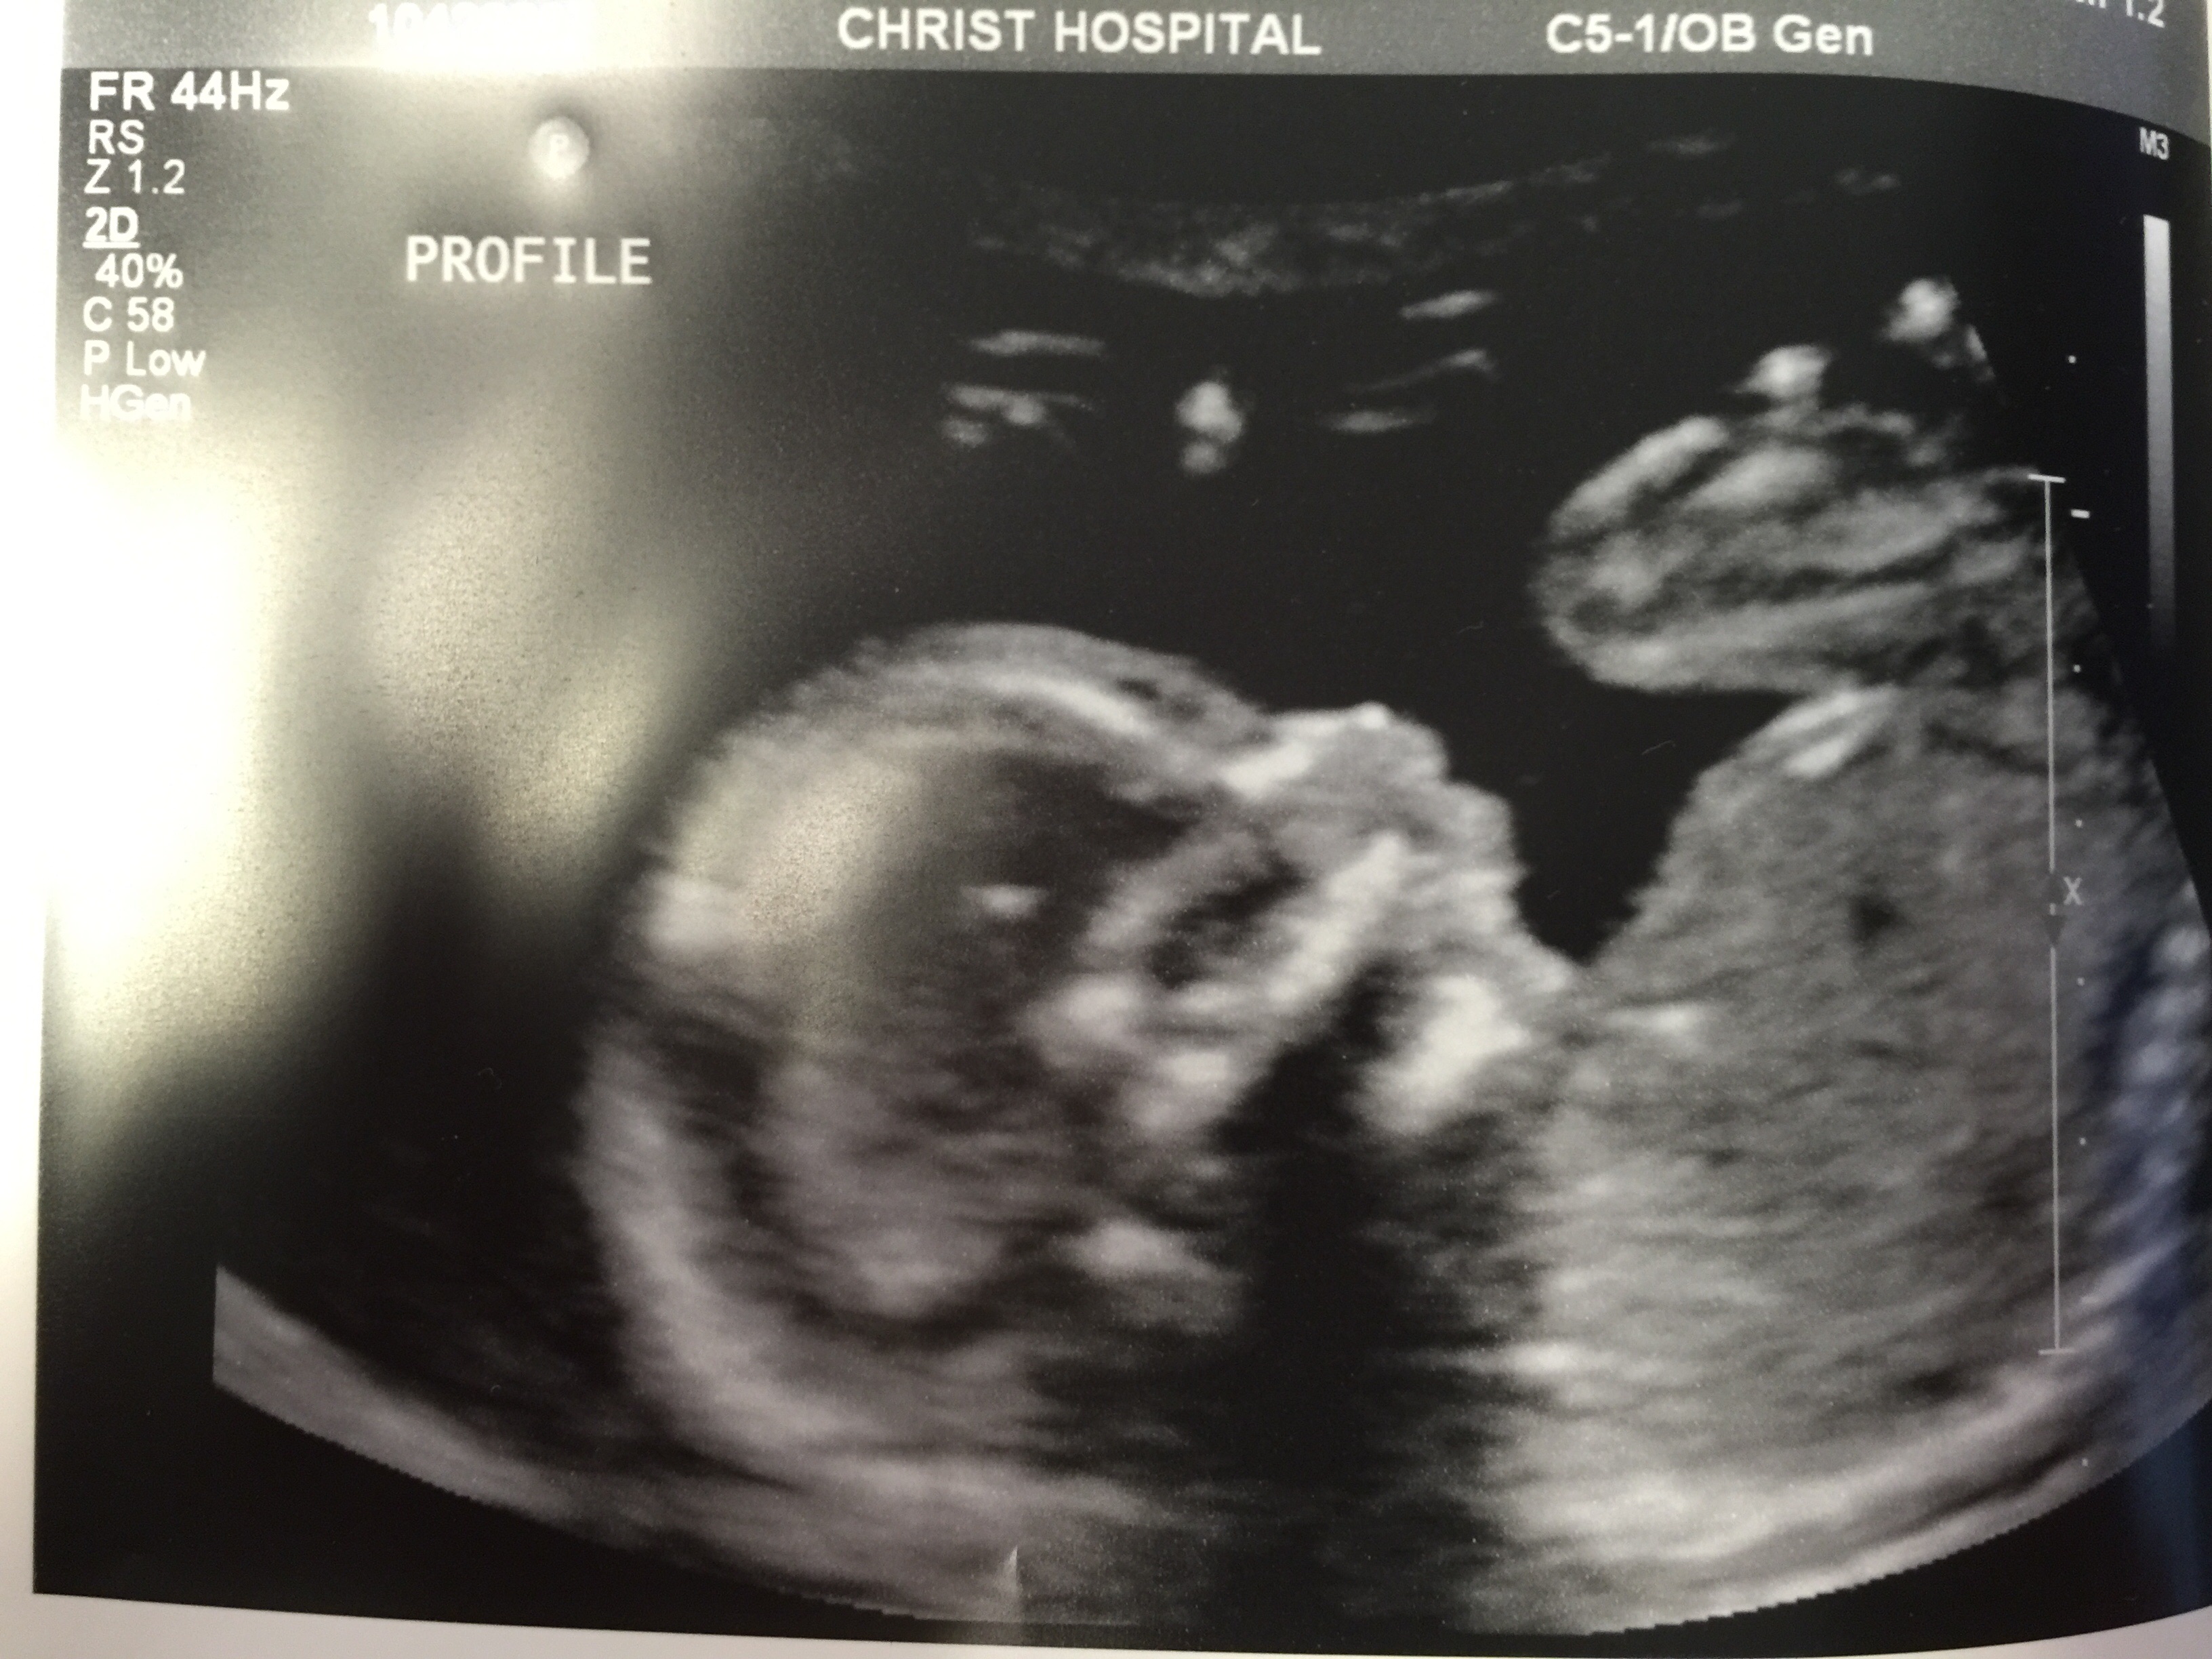

Bumps and U/S pics go here!!!